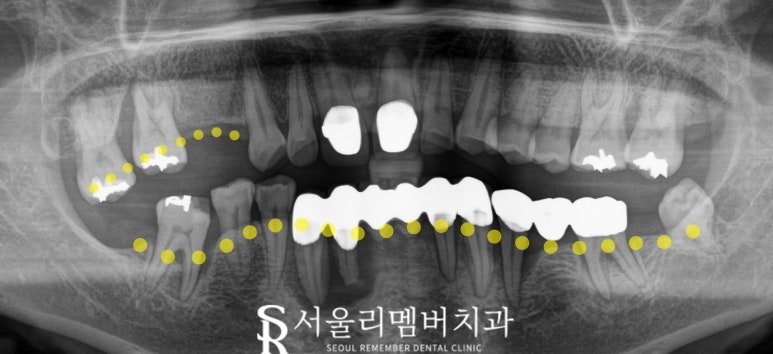

- 초진 : 전반에 걸친 염증과 흔들림

환자는 처음 내원하셨을 때

여러 치아에 염증과 흔들림을 호소하셨습니다.

오랫동안 내원을 미뤄오신 탓에

대부분의 치아 상태가 좋지 않았고,

특히 하악 쪽이 심각한 모습이었죠.

엑스레이와 구강 사진을 통해

염증 부위를 확인했을 때,

하악 전체의 발치가 필요할 정도로

악화되어 있었습니다.

위턱 오른쪽 어금니(10번대)도

마찬가지로 발치가 필요한 상황이었습니다.